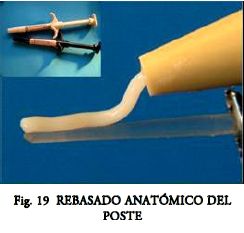

Grandini S. y col. (36), describen el “rebasado anatómico” del poste para disminuir el laminado de cemento con los mismos propósitos.

3-Rebasado Anatómico. Descrita por Grandini y Sapio (36) y Conceiçâo (20) se desarrollan para controlar el estrés de contracción.

2º.- Si el poste no refleja buena adaptación en el tercio coronario se puede recurrir a técnicas de postes accesorios y/o de rebasado anatómico (36). El objetivo es disminuir el espesor final del cemento para que actúe correctamente como junta adhesiva. También podría optarse por técnicas indirectas.

- Rebasado del Poste.- Se buscó minimizar el desajuste radicular (Fig. 13), por medio del rebasado anatómico.

De acuerdo al fabricante se pincelan dos capas generosas y sucesivas de resina fluida fotocurable (One Step, Bisco) en toda la superficie (Fig. 18). Se dejan evaporar los solventes durante 20 seg. Se eliminan los excesos con jeringa de aire. Se fotocura durante 60 seg. o más. El poste queda así plastificado y apto para recibir el material resinoso de rebase (Fig.19), (el fabricante no indica el uso de Silano y contraindica el arenado).

El poste se cubre con cemento, (Fig. 19) resina, o mezcla de ambos (mantener alejada la luz del foco) y luego se lleva el todo a posición. Durante la remoción de excesos es conveniente dejar algunas zonas de contacto coronario para que oficien de guías reposicionadoras.